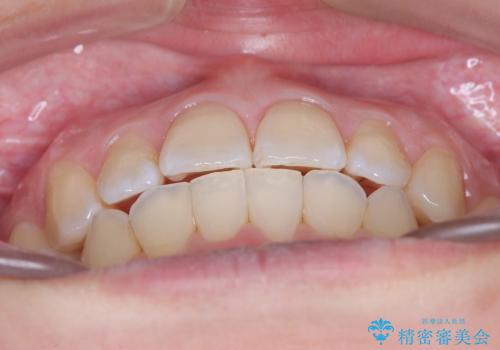

右下第二小臼歯の舌側転移の改善

- 患者様は、右下第二小臼歯が舌側に転移していることが主訴でした。診断の結果、抜歯を伴う矯正治療も検討しましたが、奥歯の遠心移動とIPR(インタープロキシマルリダクション)を行うことで、非抜歯で矯正を進めることが可能であると判断しました。治療計画では、審美ワイヤーを用いた2年間の治療で、歯列を整えつつ、臼歯関係や正中のバランスを維持しながら進めました。

非抜歯矯正では、歯の動きを慎重に調整することが求められます。本症例では、奥歯を遠心に移動させることで、舌側に転移した右下第二小臼歯の位置を改善しました。また、IPRを行うことで歯間スペースを確保し、無理なく歯列の調整を行いました。非抜歯での治療は、特に臼歯関係や正中を保ちながら治療できるというメリットがあり、最終的にはバランスの取れた歯並びを実現できました。審美ワイヤーを使用したことで、治療中も目立ちにくく、患者様の見た目にも配慮した治療を行いました。